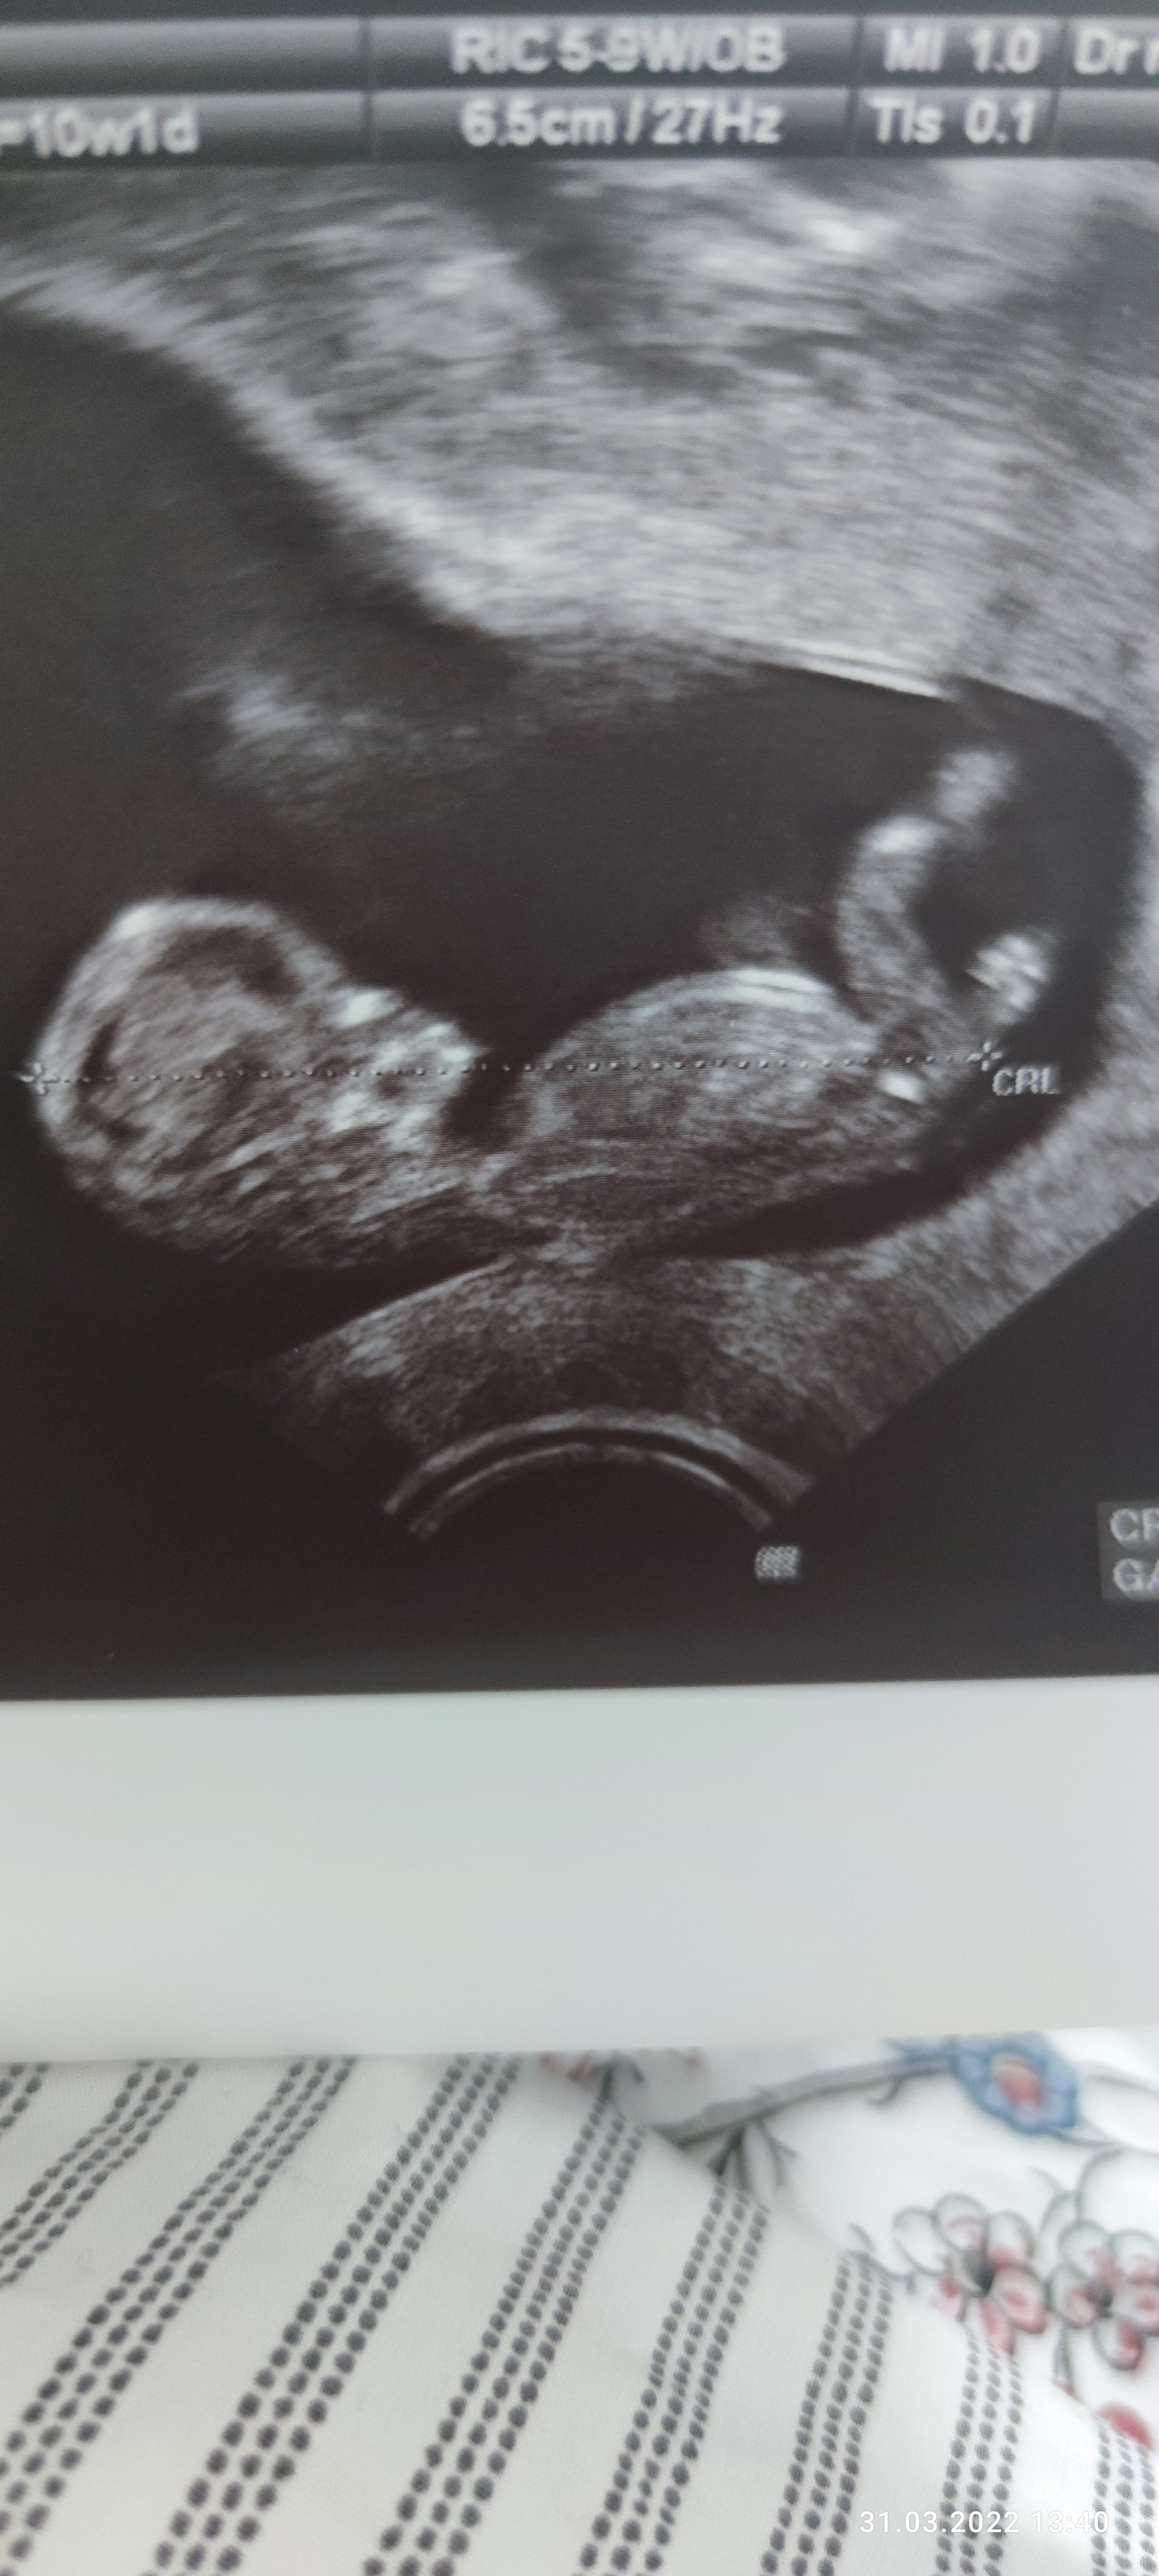

Zdjecie z 10 tygodnia wg. Miesiaczki, z usg 11 tydzien.

Lekarz twierdzi, ze chlopak( powiedzial, ze przypuszcza). Mi tez sie tak wydaje. A jakie jest Wasze zdanie? Czy takowe narzady moga moze jednak nalezec do pannicy?